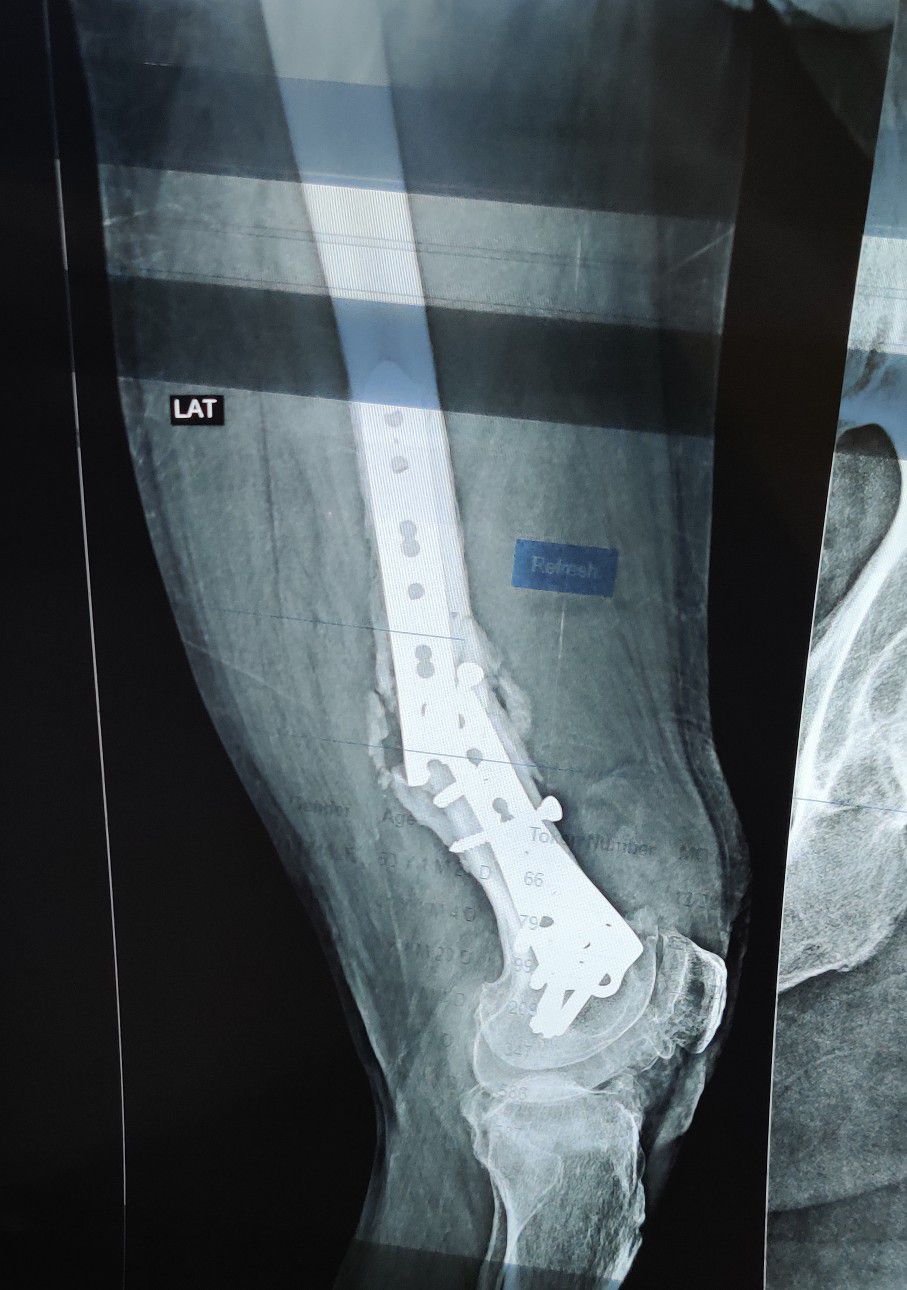

Broken Intramedullary Nail Femur

Xray

Fracture

Femur